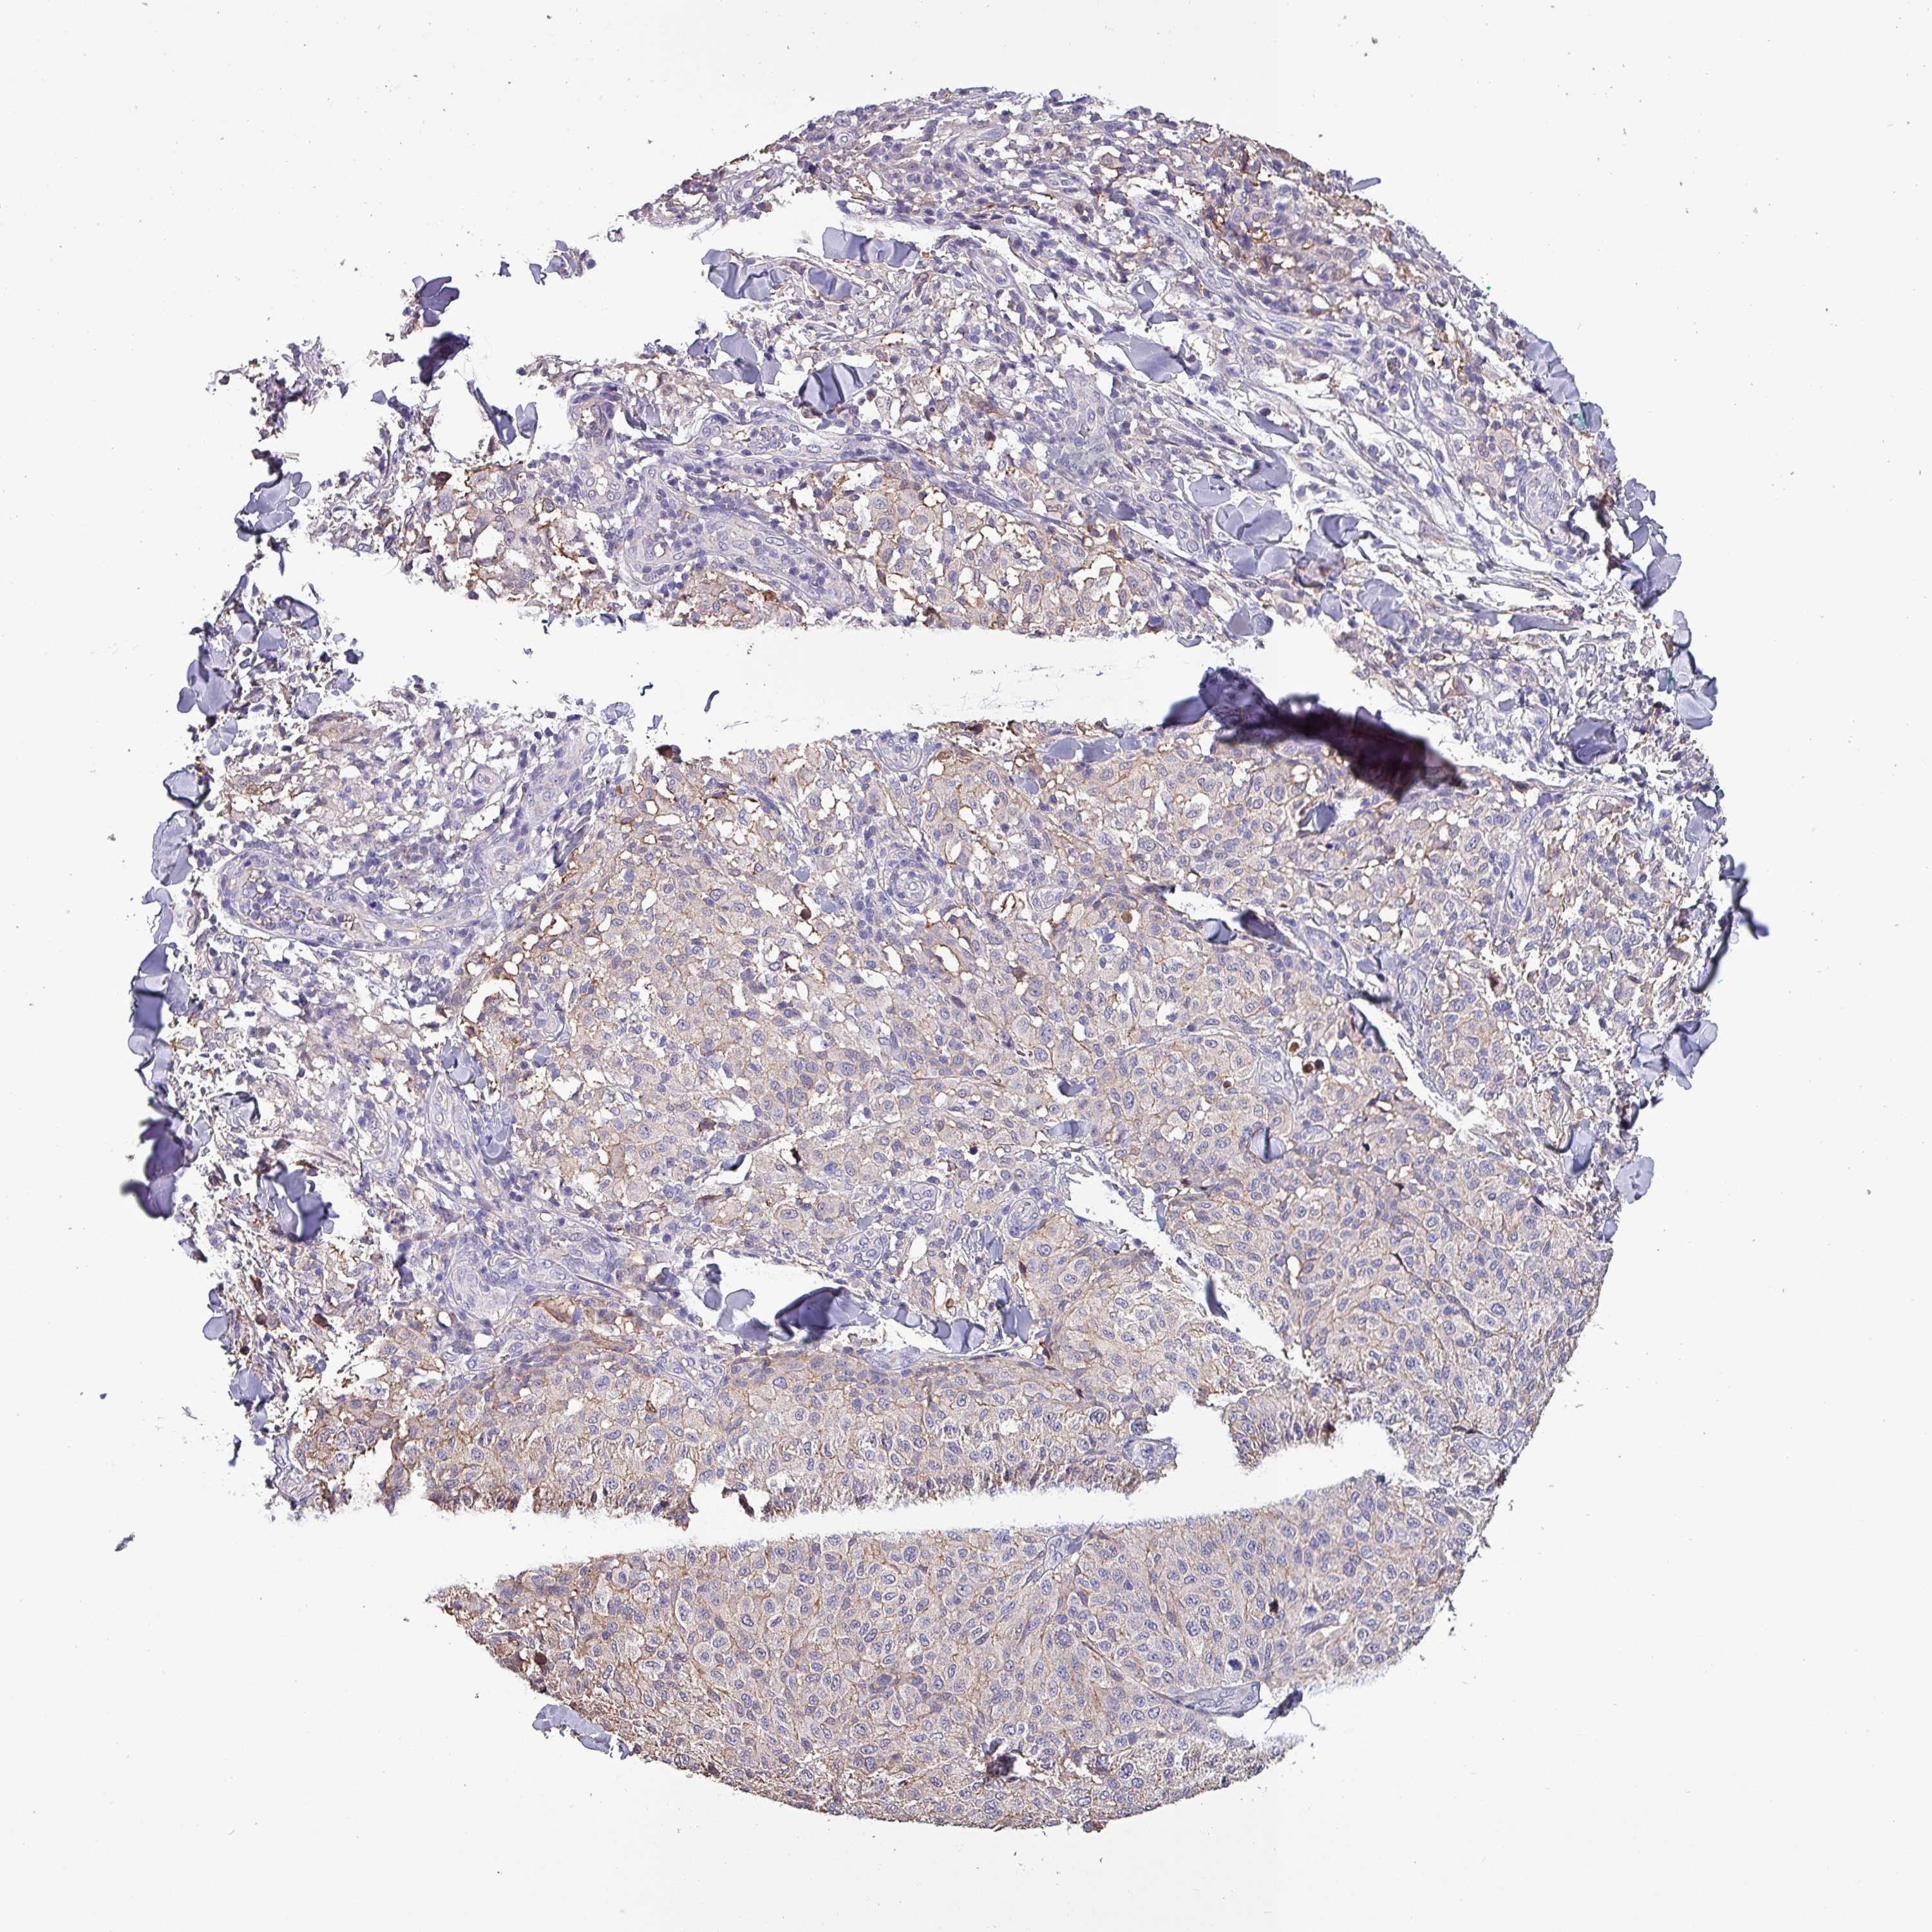

MELANOMA - Protein expressioni

A mouse-over function shows sample information and annotation data. Click on an image to view it in a full screen mode. Samples can be filtered based on level of antibody staining by selecting one or several of the following categories: high, medium, low and not detected. The assay and annotation is described here.

Note that samples used for immunohistochemistry by the Human Protein Atlas do not correspond to samples in the TCGA dataset.

Antibody stainingi

Antibody staining in the annotated cell types in the current human tissue is reported as not detected, low, medium, or high, based on conventional immunohistochemistry profiling in selected tissues. This score is based on the combination of the staining intensity and fraction of stained cells.

Each image is clickable and will lead to virtual microscopy that enables deeper exploration of all samples and also displays staining intensity scores, fraction scores and subcellular localization as well as patient and tissue information for each sample.

Antibody HPA045402

Staining

High

Medium

Low

Not detected

Intensity

Strong

Moderate

Weak

Negative

Quantity

>75%

75%-25%

<25%

None

Location

Nuclear

Cytoplasmic/membranous

Cytoplasmic/membranous,nuclear

Malignant melanoma, NOS

Malignant melanoma, Metastatic site